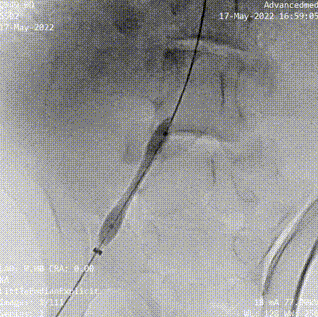

(腎動脈導(dǎo)絲遞進)